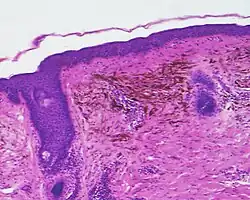

The blue colour is caused by the pigment being deep in the skin.[3]

Histopathology